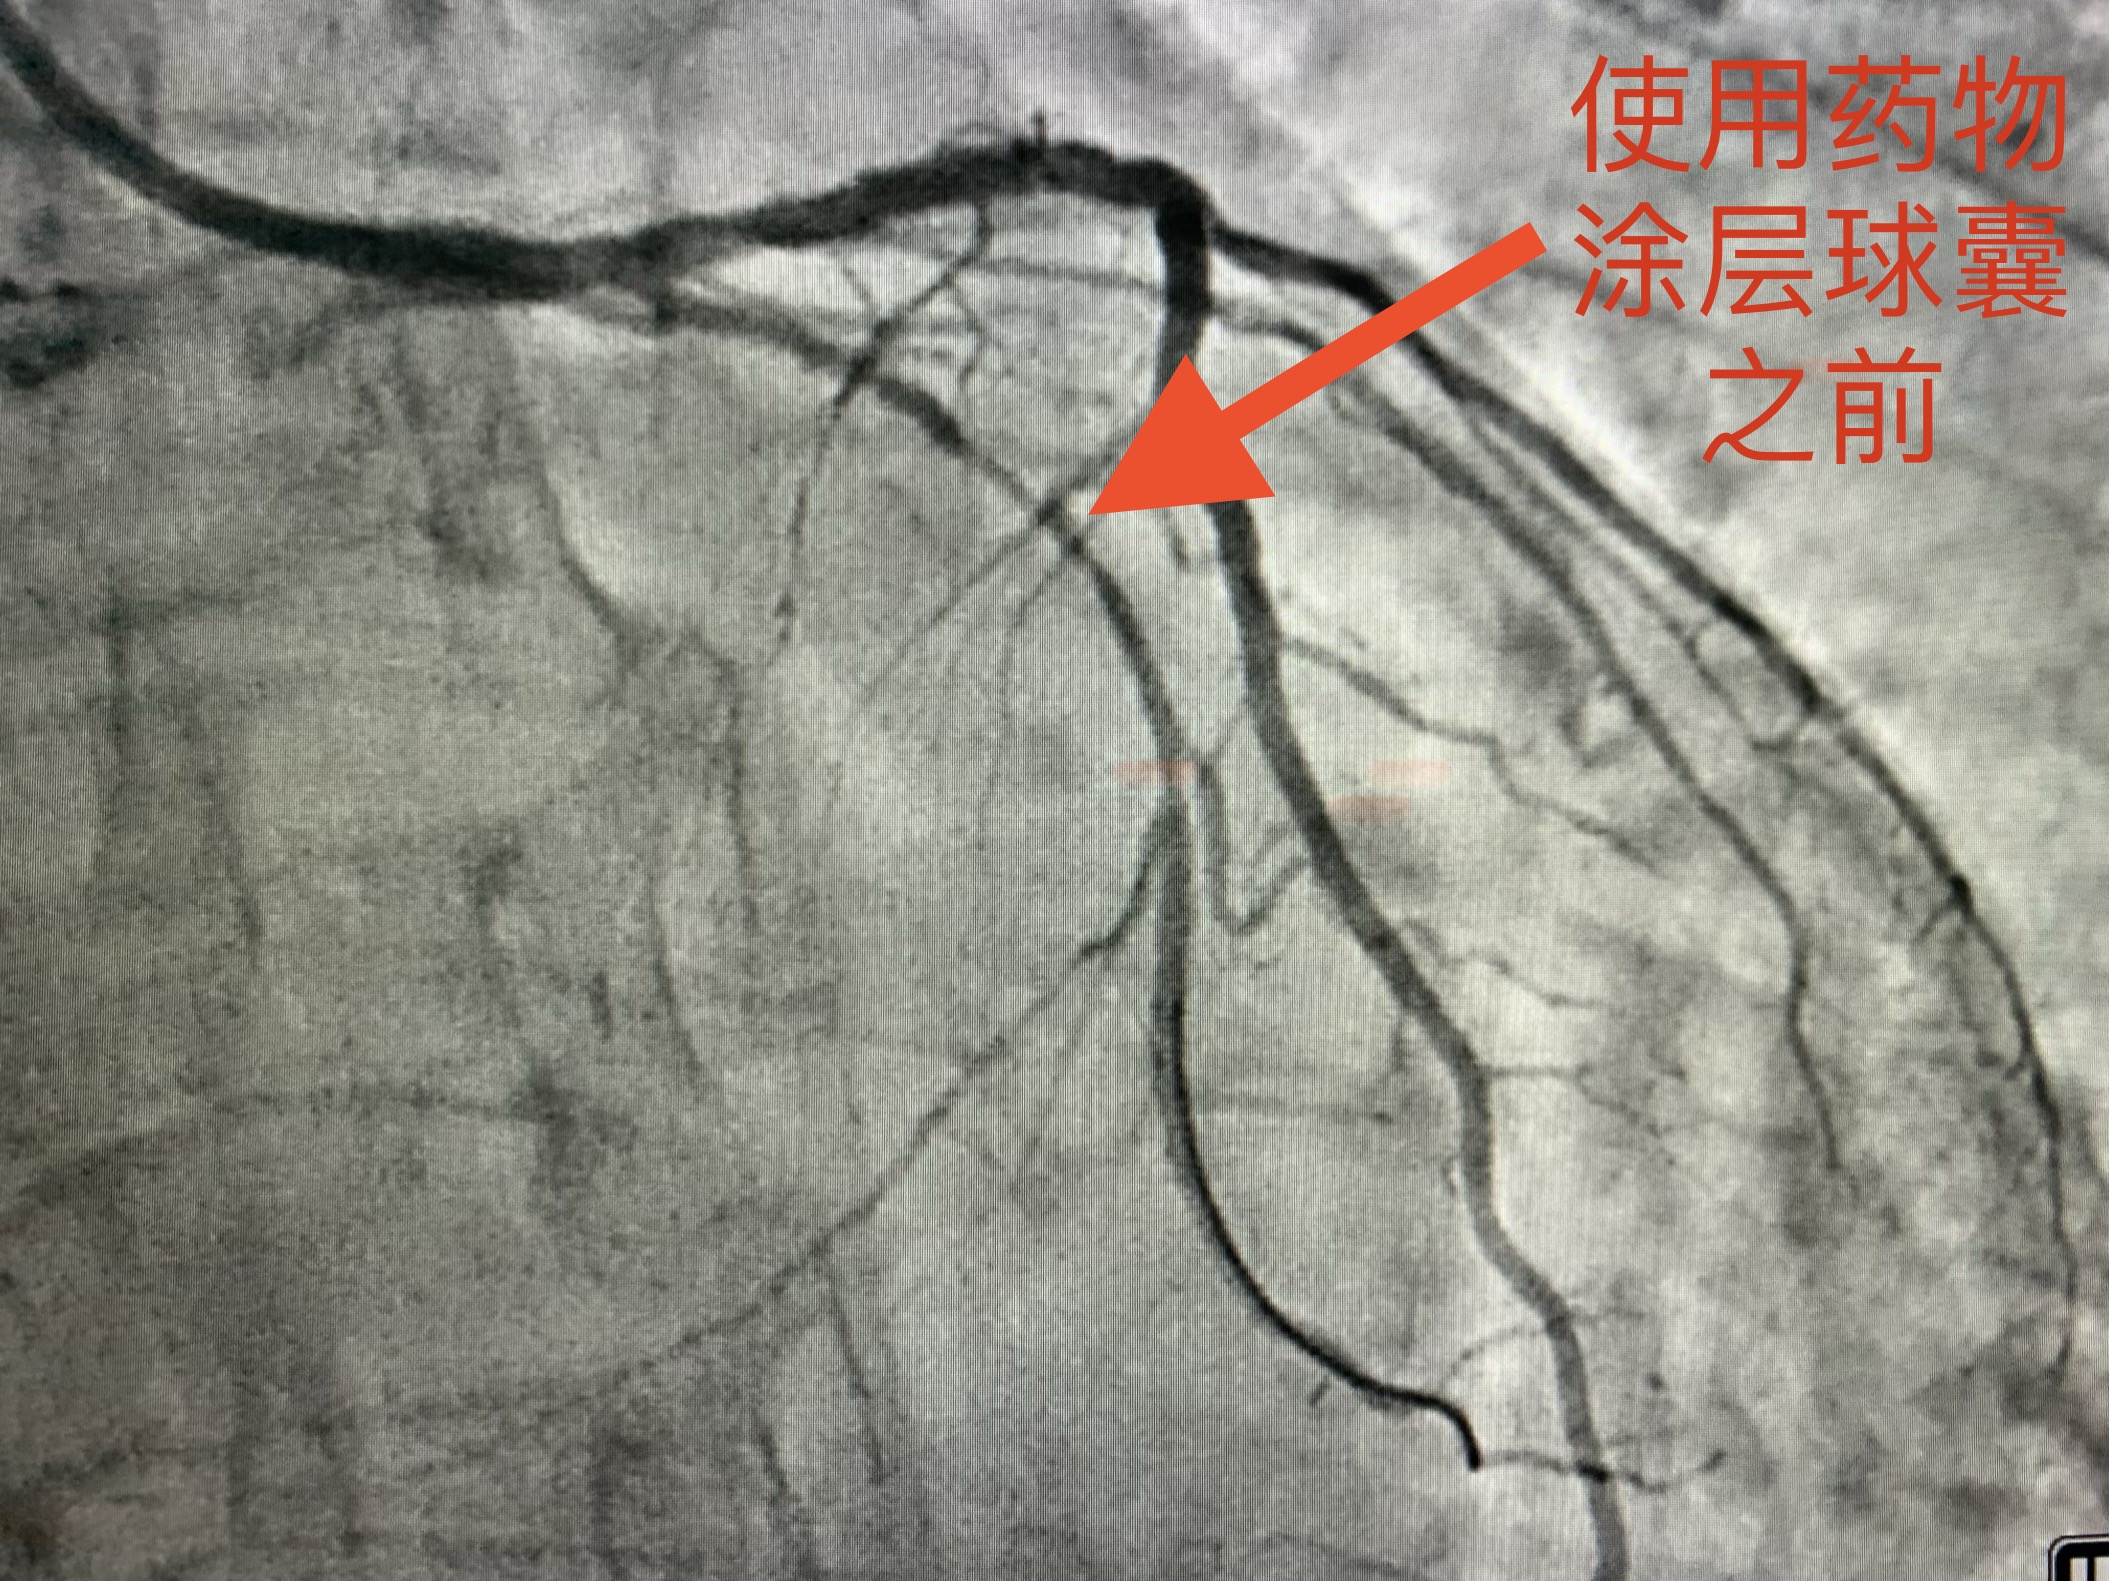

果然不出所料,通过复查冠脉造影、并与上次冠脉支架植入术后造影结果对比发现:患者左冠系统原植入支架内未见明显狭窄,左冠其余血管节段未见明显狭窄、不稳定斑块及血栓等,血流通畅、达TIMI3级;但回旋支近段、中段分别可见新发严重狭窄,血流偏慢。(造影结果见下图)

考虑到老赵的回旋支比较细小,直径约为2.0-2.25mm,如果植入小直径的支架血管发生再狭窄的概率较高。经过心血管介入团队的讨论,一致决定术中使用药物涂层球囊介入治疗。这就是心血管界内最近比较火的入治疗的新理念——介入无植入。